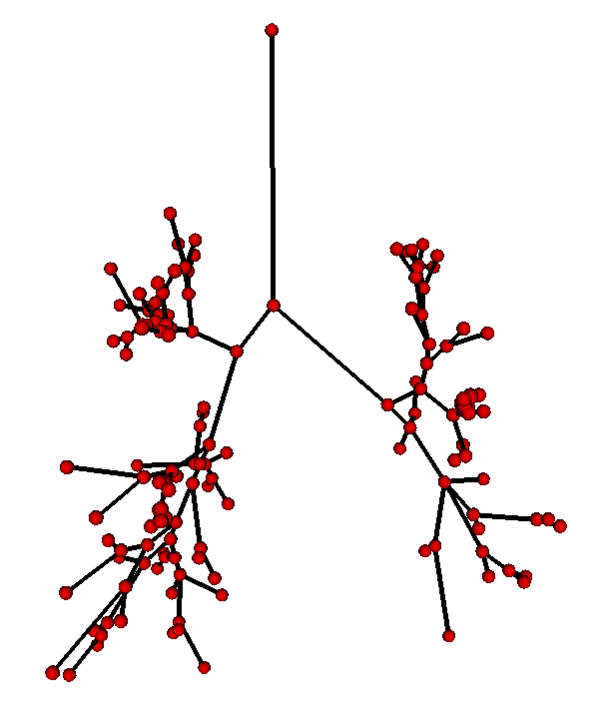

Segmentation - adaptive region growing (left), extracting centerlines - topologically and geometrically correct thinning (middle), and excluding branch-areas based on 3D distance map calculation (right).

Partitioning centerlines in a formal tree data structure (left), partitioning segmented tree via isotropic label propagation (middle), and quantitative analysis formal XML tree with associated measurements (right).